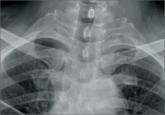

ArticleProvisional Mini-Fragment Plate Fixation in Clavicle Shaft FracturesAuthor:Castillo TNPublish date: October 10, 2013 Plate fixation has an increasingly prominent role in the management of select clavicle fractures. Read More